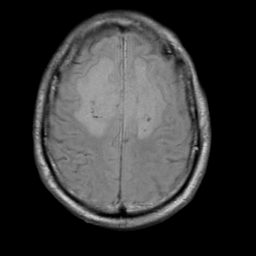

Meningioma, MR Study #2 -- Slice #15

[Home][Help][Clinical] Slice 15